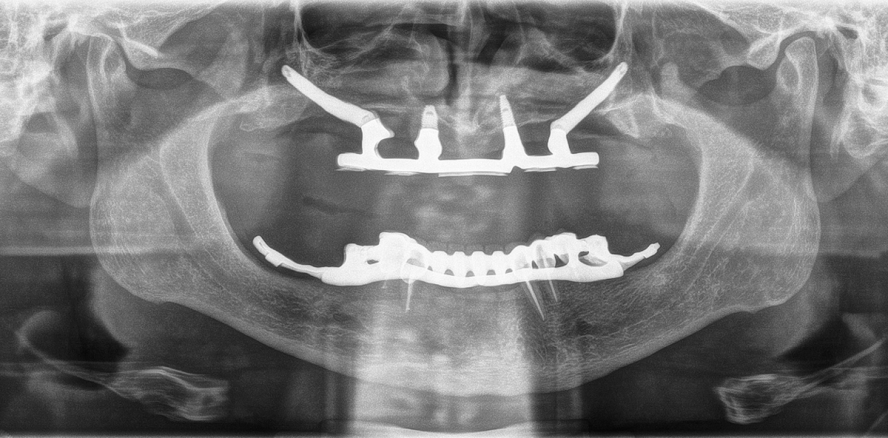

Ein 59-jähriger Patient wurde erstmals in die Abteilung für Mund-, Kiefer- und Gesichtschirurgie des Marienhospitals Stuttgart überwiesen zur implantologischen Neuversorgung nach völligem Implantatverlust im Oberkiefer. Im Unterkiefer bestand eine Restbezahnung von 35, 34, 33, 43 und 44, die Zähne allesamt endodontisch behandelt mit Sondierungstiefen von 3–4 mm und radiologisch ohne periapikale Auffälligkeiten. Die Zähne waren als Pfeiler verblockend überkront mit 32–42 als Brückenzwischenglieder sowie an den Pfeilerzähnen 35 und 44 jeweils eine Matrize zur Verankerung einer Geschiebeprothese. Wunsch des Patienten war ein stabiler Zahnersatz im Oberkiefer. Aufgrund u. g. Besonderheiten war ein Halt der vorhandenen Totalprothese im Oberkiefer nicht gewährleistet, weshalb diese überwiegend nicht getragen wurde. Die Anamnese ergab bis auf einen Diabetes mellitus Typ II keine wesentlichen Risikofaktoren. Die klinische und radiologische Diagnostik (OPG, FRS, CT-Gesicht) zeigte einen Knochendefekt des Oberkiefers mit Totalverlust des zahntragenden ­Anteils und beider Kieferhöhlen (Abb. 1 und 2). Der knöcherne Hartgaumen und Nasenboden wies eine Restknochenhöhe von lediglich 1–2 mm auf. Wei­terhin bestand eine Diskrepanz mit erheblicher Verkürzung in der Transversal- und Sagittalebene (Abb. 2).

Nach zweiwöchiger Gingivakonditionierung wurde eine Oberkieferabformung mit Impregum® auf Implantatniveau unter Verwendung des Impression Coping Open Tray Systems von Brånemark® genommen. Die vertikale und sagittale Relation wurde durch einen Wachswall bestimmt und eine zen­trische Bissnahme durchgeführt. Nach Anfertigung und Anprobe der Wachs­aufstellung wurde im zahntechnischen Meisterlabor ein individueller Präzi­sionssteg nach Dolder® angefertigt. Der Steg wurde im Mund auf seinen passiven Sitz und radiologisch auf seine Passgenauigkeit geprüft (Abb. 10). Mit der Gerüsteinprobe wurden alle funktionellen und ästhetischen Parameter nochmals überprüft und die Hybridprothese fertiggestellt. Der individuelle Steg wurde mit einem Drehmoment von 35 Ncm verschraubt und die Implantat-Steg-Rekonstruktion mit einem OPG überprüft (Abb. 11).